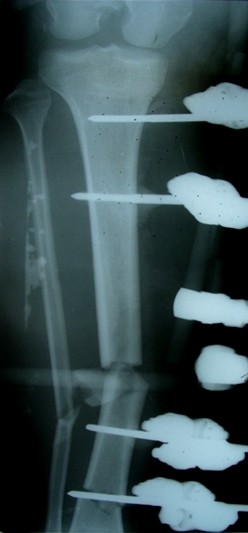

Больной 27 лет, мотоциклист. Поступил 23.04.10

ДЗ. О. перелом н.з левого бедра Gustillo 3b (c повредрение бедренной вены),

О.Правого бедра Gustillo 2, з. фрагментарный перелом левой голени.

При поступлении Hb 66 ISS 40, фиксация стержневыми аппратами, сосудистые

хирурги выполнили шов вены. Выполена резекция бедренной кости 9 см

В настоящий момент планируем. Переход со стержневых аппаратов на стержни с

антибактериальным покрытием на правом бедре и левой голени.

Левое бедро пранируем продолжить фиксировать в стержневом аппрате.

Вопрос: что делать с левым бедром? Учитывая внутрисутавной характер

перелома, дефект бедра 9 см.